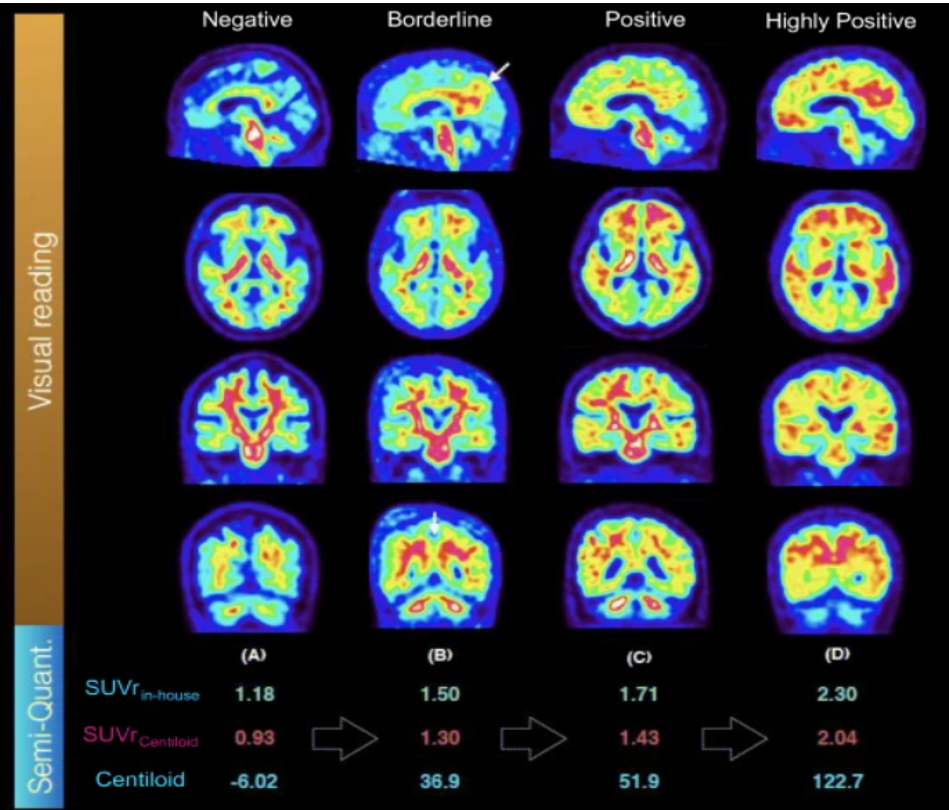

Result 3. Florbetapir PET의 Centiloid scale 측정

❓ Centiloid란?

아밀로이드 베타 PET 영상의 정량화를 위한 표준화된 척도로, Centiloid 값이 높을수록 뇌 내 아밀로이드의 축적이 많다는 것을 의미해요! 아래 사진에서 왼쪽에 위치한 정상인의 뇌와 알츠하이머병을 가질 가능성이 높은 뇌를 비교할 때, 오른쪽으로 갈수록 나타나는 Centiloid값이 높아지는 것을 확인할 수 있어요.

첨부 이미지

• Donanemab 투여량에 따른 centiloid 수치 변화

맨 오른쪽에 위치한 10mg/kg를 나타내는 연두색 박스를 제외하고 모든 3.0mg/kg 이하의 낮은 약물 투여량에 대해서는 centiloid 변화가 0 주위에 위치하는 것을 보아 유의미한 아밀로이드 감소가 나타나지 않는다는 것을 알 수 있어요!

이에 반해 10mg/kg 투여시에는 centiloid 변화가 평균 -44.4로 나타나, 뇌 아밀로이드가 약 40~50% 감소되었다는 것을 볼 수 있어요! 😉

이를 통해 10mg/kg 투여시 효과적으로 뇌내 아밀로이드 축적을 감소시킬 수 있다는 것이 확인되었어요!